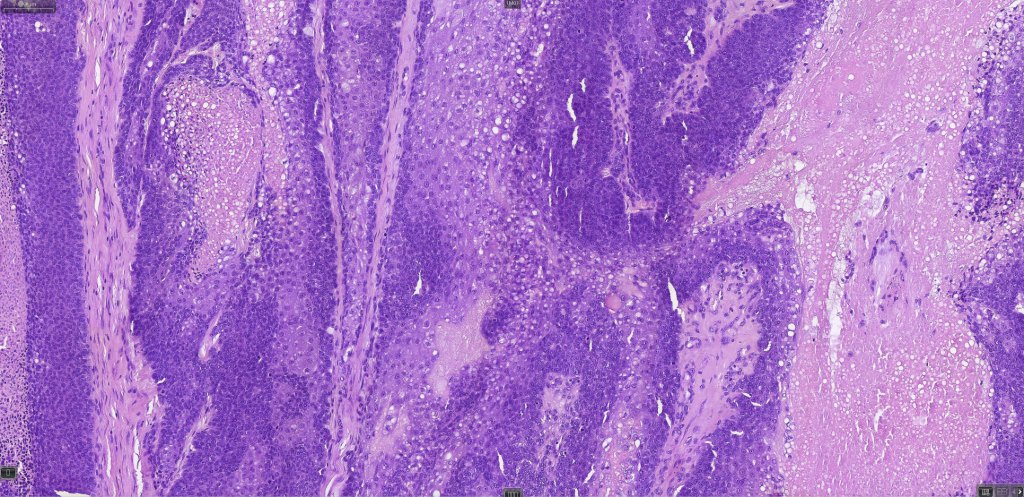

Histological features

•Well differentiated lobular growth pattern though to a poorly differentiated tumor often showing a diffuse, infiltrating border which may extend into the subcutaneous fat

•Comedo type necrosis commonly present

•Tumors are composed of an admixture of darkly staining basaloid cells with hyperchromatic or vesicular nuclei and more obvious sebaceous cells with eosinophilic, bubbly, multivacuolated cytoplasm frequently indenting the nucleus (scalloped)

•Often mitoses are numerous and abnormal forms evident

Sebaceous carcinoma from a patient with Muir-Torre syndrome kindly shared by Dr. Antonina Kalmykova.